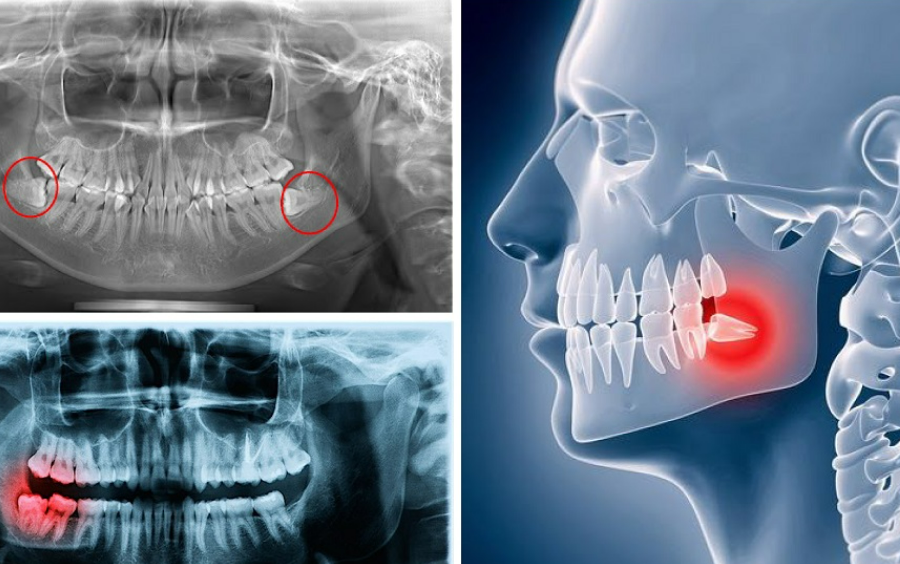

Răng khôn (răng số 8) là chiếc răng cuối cùng mọc trên cung hàm. Răng khôn giống như một chiếc răng thừa của hàm răng bởi nó không có khả năng thực hiện chức năng ăn nhai.

Bởi vì là răng mọc lên cuối cùng, trong khi cung hàm không đủ chỗ trống nên răng khôn thường có xu hướng mọc ngầm, mọc lệch, mọc ngang, xô đẩy các răng bên cạnh, gây ra nhiều hậu quả như: